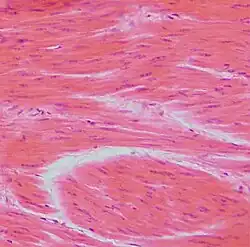

Smooth Muscle Cells

Cardiac Muscle